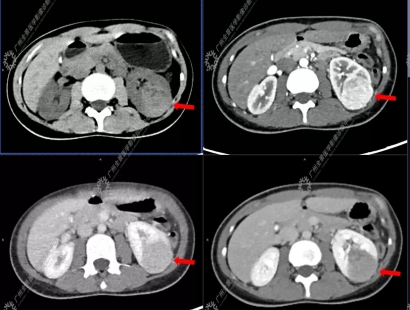

24岁的陈女士(化名)无明显诱因出现右肩背部疼痛、呼吸困难5天,在当地医院检查提示右侧液气胸,右肺压缩近98%,遂留置胸腔闭式引流管,同时肺部CT发现双肺多发“肺大泡”。在住院期间患者常规超声检查偶然发现左肾下极一较大肿块。当地医院CT检查提示为肾癌合并肾门淋巴结转移。为进一步全面评估患者分期,医生建议行petct全身检查。

检查提示陈女士右侧少量气胸,双肺散在薄壁空腔;左肾下极稍高密度肿块,糖代谢轻度增高(SUVmax为3.40);左肾门增大淋巴结,糖代谢未见增高。综合考虑肺淋巴管肌瘤病,左肾下极肿块为乏脂肪型错构瘤可能性大,需鉴别肾癌。

由于左肾肿块较大,陈女士决定手术治疗,最终左肾肿块病理诊断:血管平滑肌脂肪瘤,这一检查结果与petct诊断结果不谋而合。